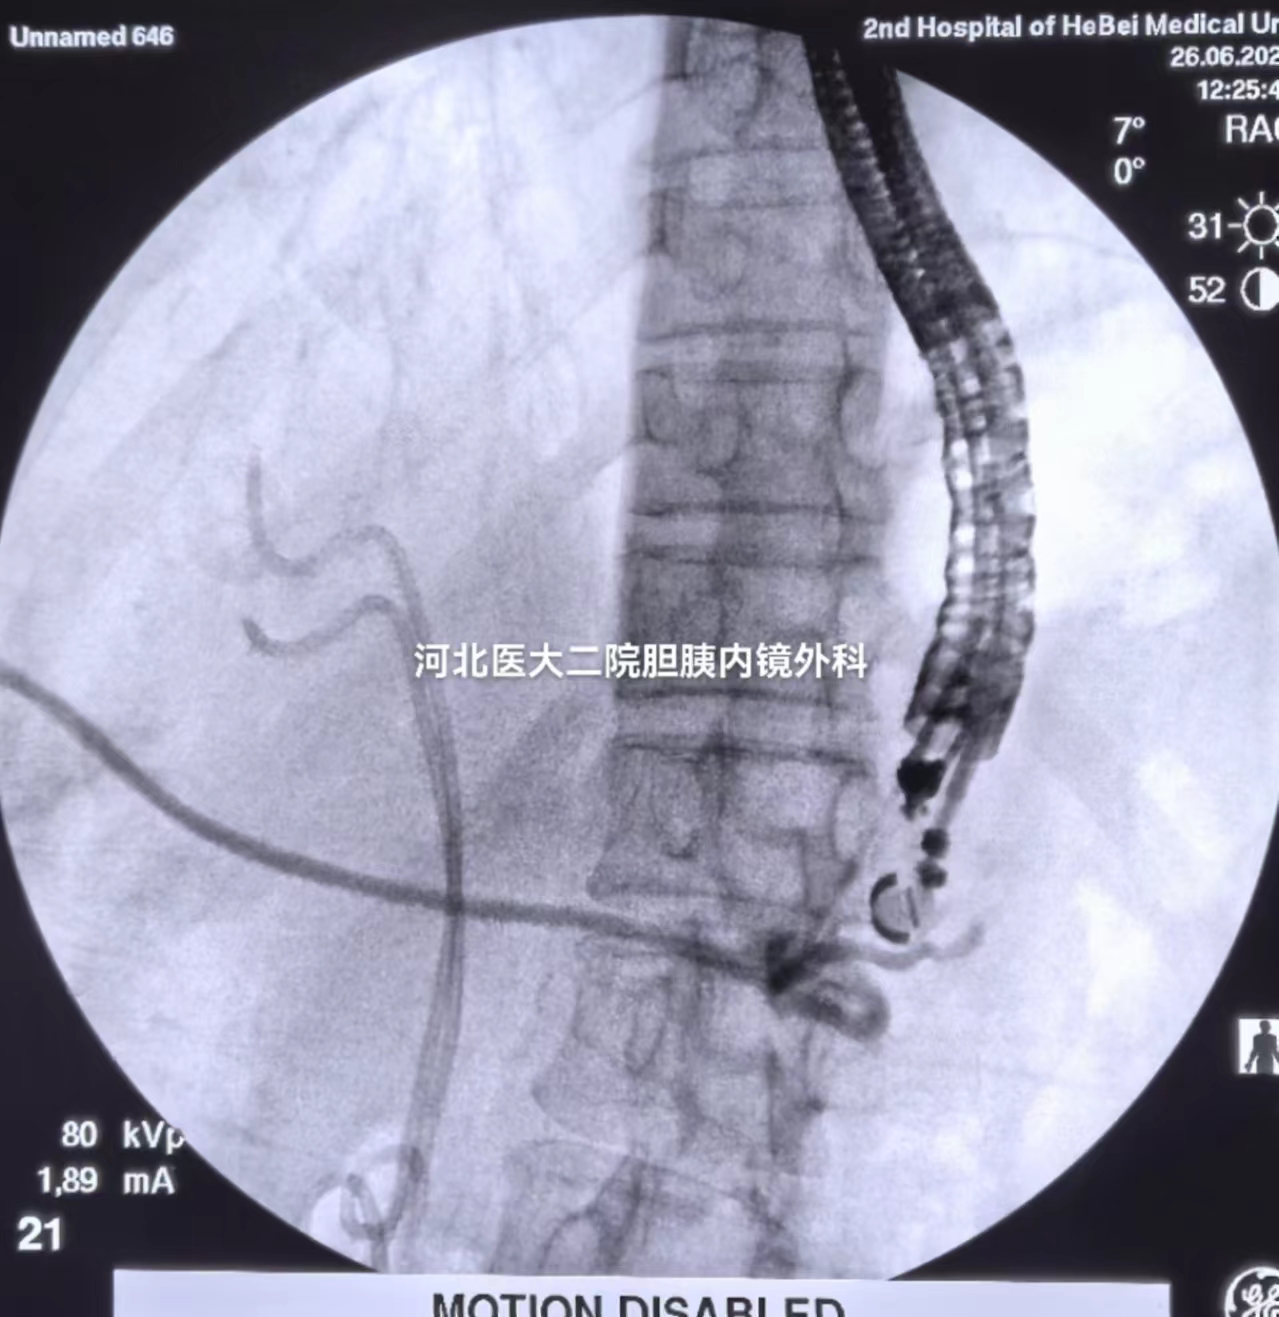

造影

微信图片_20240814194352.jpg

见胰管及引流管显影,置入导丝